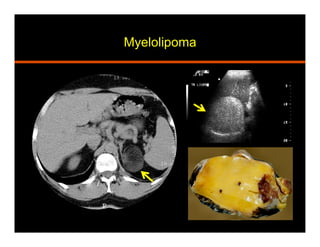

Myelolipoma

•  Benign and non functioning tumor

•  Mature adipose and hematopoeitic tissue

•  Heterogeneous, pseudo-capsule, calcifications

•  US: hyperechoic lesion

•  CT: macroscopic fat (HU<30)

•  MRI: T1 hyperintense signal suppresses with fat sat

India ink (chemical shift) artifact at myeloma-adrenal

interface and within the mass on out of phase

Ax Cor